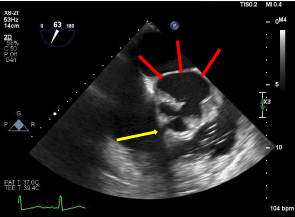

CTA of the aorta was performed, which revealed a 4.6 cm x 3.5 cm saccular outpouching along the posterior aspect of the aortic root and sinuses of Valsalva. These findings were consistent with a sinus of Valsalva aneurysm, which appeared to arise from the left coronary sinus. Imaging study was negative for aortic dissection. The patient then underwent a transesophageal echocardiogram (TEE), which demonstrated a tri-leaflet aortic valve with thick echodensities strongly suggestive of vegetations. TEE further revealed dilatation of the left sinus of Valsalva [Figure 2], severe aortic insufficiency, mild mitral and tricuspid regurgitation. Coronary angiogram was consistent with moderate non-obstructive coronary artery disease.

Figure 3.  Parasternal long access view of bedside TEE, demonstrating thick aortic valve  echodensities, suggestive of vegetations (yellow arrows), and left coronary  sinus of valsalva (red arrows)

It has been documented that right coronary sinuses are usually most commonly affected (65-85%), followed by non-coronary sinus (10-30%), with only less than 5% in the left coronary sinus [8]. Sinus of Valsalva aneurysm rarely arises from the left coronary sinus due to external support from the right ventricle and the pulmonary trunk [1].  When SOVA is suspected, it is vital to identify its location because patient symptoms are linked to the size of the aneurysm, the site of rupture, and the speed at which the rupture occurs. Rupture of the right and noncoronary sinuses can lead to a left to right shunting of blood by forming a communication between the aorta and either the right atrium or the right ventricular outflow tract [2]. This ultimately can cause severe hypoxia, decreased cardiac output, and severe right heart overload. Left coronary SOVA rupture as seen in this patient, however, can be clinically less significant as it causes communication with the left atrium or the left ventricular outflow tract, keeping the heart’s hemodynamics relatively unchanged. Due to its less dangerous clinical presentation, a left coronary SOVA rupture can be present chronically, and only causes significant symptoms when superimposed with another condition that interferes with cardiac hemodynamics, such as deteriorating valvular disease, endocarditis, pulmonary embolism, and myocardial ischemia [1,4] [Figure 4].

Figure 4. TEE demonstrating ruptured aortic root at the level of the left sinus of  Valsalva (red arrows)